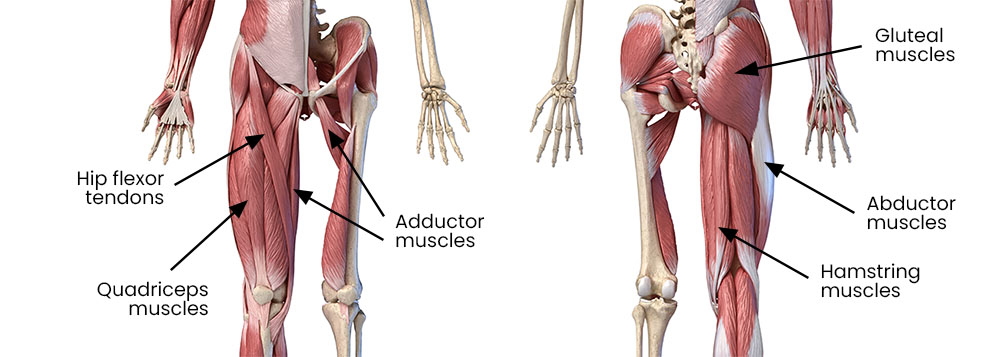

You have 4 main muscle groups that move your hips. They are the:

- gluteal (buttock) and hamstring muscles at the back

- abductor muscles on the outside of your hip

- flexors at the front (your quadriceps are part of this group)

- adductors on the inside of your thigh.

Tendons attach your muscles to your bones.